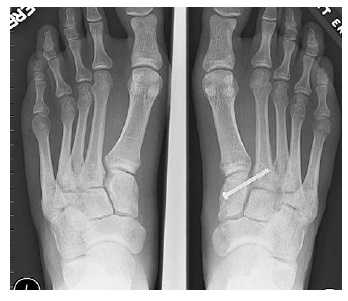

Отдельно стоит разобрать тему разрыва связки Лисфранка с изолированной нестабильностью 2 предплюсне-плюсневого сустава. Частота данного повреждения значительно выросла за последние 50 лет в связи с популяризацией спорта. Также крайне высота частота отсроченной постановки диагноза. При этой патологии пациента беспокоит боль по тыльной поверхности 1-2-3 предплюсне-плюсневых суставов при физической нагрузке. Часто при осмотре удаётся обнаружить деформацию в данной области. Если осмотр производится отсрочено через несколько недель или месяцев после травмы то клинически определить нестабильность уже не удастся, однако на рентгенограммах с нагрузкой будет виден диастаз между медиальной клиновидной костью и основанием 2 плюсневой кости.

В случаях этого повреждения показано оперативное лечение, открытое устранение подвывиха основания 2 плюсневой кости с фиксацией винтом. Устранение подвывиха производится из доступа в 1 межплюсневом промежутке, рубцовая ткань и остатки связки могут интерпонировать сустав, тогда потребуется их удалить. После вправления производится предварительная фиксация спицей и рентгенологический контроль.

Затем устанавливается винт соединяющий основание 2 плюсневой кости и медиальную клиновидную кость.

После операции следует 6-12 недельный период иммобилизации в жёстком ортезе без осевой нагрузки на ногу. Затем нагрузка постепенно увеличивается до полной в течение 4-6 недель.

Данный метод оперативного лечения эффективен в течение первых 6-8 месяцев после травмы. В случае если с момента травмы прошло больше времени целесообразно выполнение артродеза.

Удаление винта производится через 6-12 месяцев после операции. В случае формирования болезненного посттравматического артрита 2 предплюсне-плюсневого сустава также показано выполнение его артродеза.